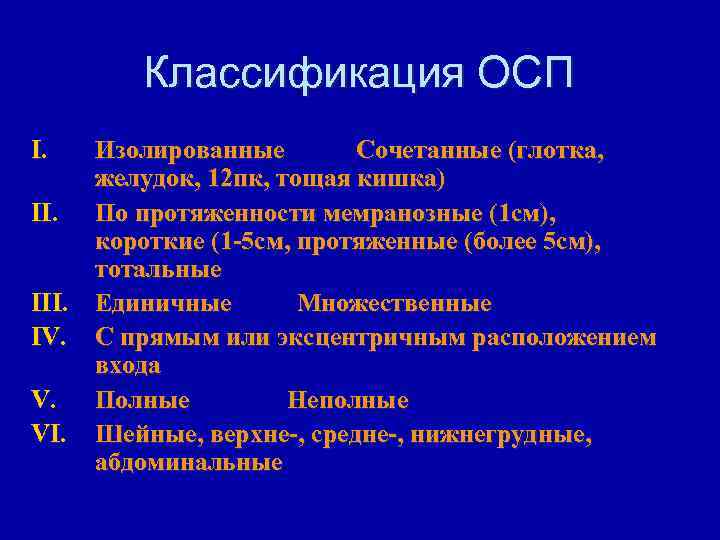

Классификация ОСП I. Изолированные Сочетанные (глотка, желудок, 12 пк, тощая кишка) II. По протяженности мемранозные (1 см), короткие (1 -5 см, протяженные (более 5 см), тотальные III. Единичные Множественные IV. С прямым или эксцентричным расположением входа V. Полные Неполные VI. Шейные, верхне-, средне-, нижнегрудные, абдоминальные